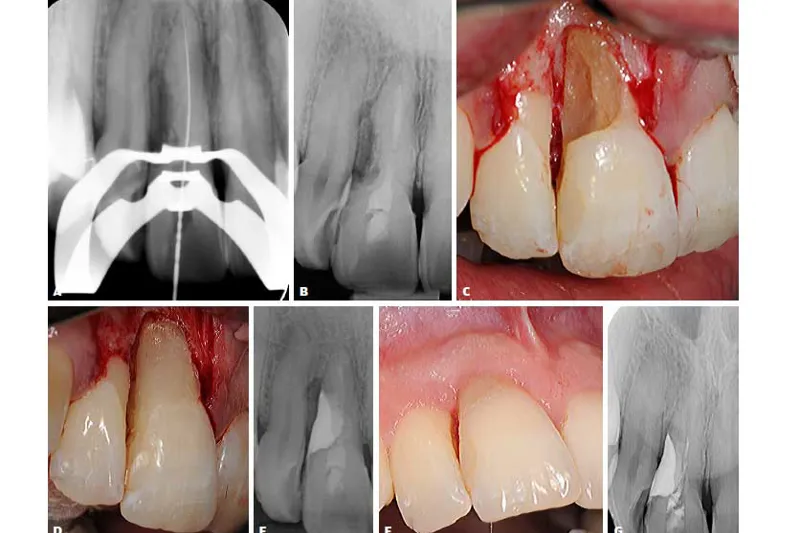

I denne artikel beskrives eksempler på eksterne resorptionsforløb samt efterfølgende behandlinger, svarende til en tidlig reparationsrelateret overfladeresorption (ikke-infektion) samt senstadier af infektionsrelaterede inflammatoriske resorptioner på patienter med traumebelastede tandrødder. Den nekrotisk og bakterielt inficerede pulpa kan opretholde en resorption aktiv, og den eksterne resorption kan kompromitteres ved en parodontalt betinget infektion.

I det første patienttilfælde gennemgås et fejlagtigt behandlingsforløb samt vanskelighederne ved at opnå et klart diagnostisk grundlag omkring en tidlig reparationsrelateret overfladeresorption. I de efterfølgende to patienttilfælde redegøres for diagnostik, specifik behandling samt kontrol af den infektionsrelaterede resorptive proces med en infektiøs kontaminering marginalt.

Forkert diagnostik af traumerelaterede eksterne rodresorptioner kan føre til iværksættelse af rodbehandling, som kunne have været undgået. Første patienttilfælde viser, at en ortodontisk behandling i tilknytning til tand med traumehistorik kan føre til udvikling af overfladeresorption. For at undgå en endodontisk fejlbehandling skal vitaliteten af tanden så vidt muligt undersøges, hvorved en infektionsrelateret inflammatorisk resorption kan udelukkes. I stedet skal man seponere ortodontisk apparatur fra den aktuelle tand. De to afsluttende patienttilfælde viser, at ved større inflammatoriske resorptioner kan der opstå marginal kommunikation, og tilstødende ny infektion kan derfor være parodontalt betinget. Kirurgisk behandling og forsegling af store eksterne resorptionskaviteter er afgørende for en god prognose, og denne procedure viser i dette arbejde standsning af den eksterne resorption i begge patienttilfælde over lang tid.